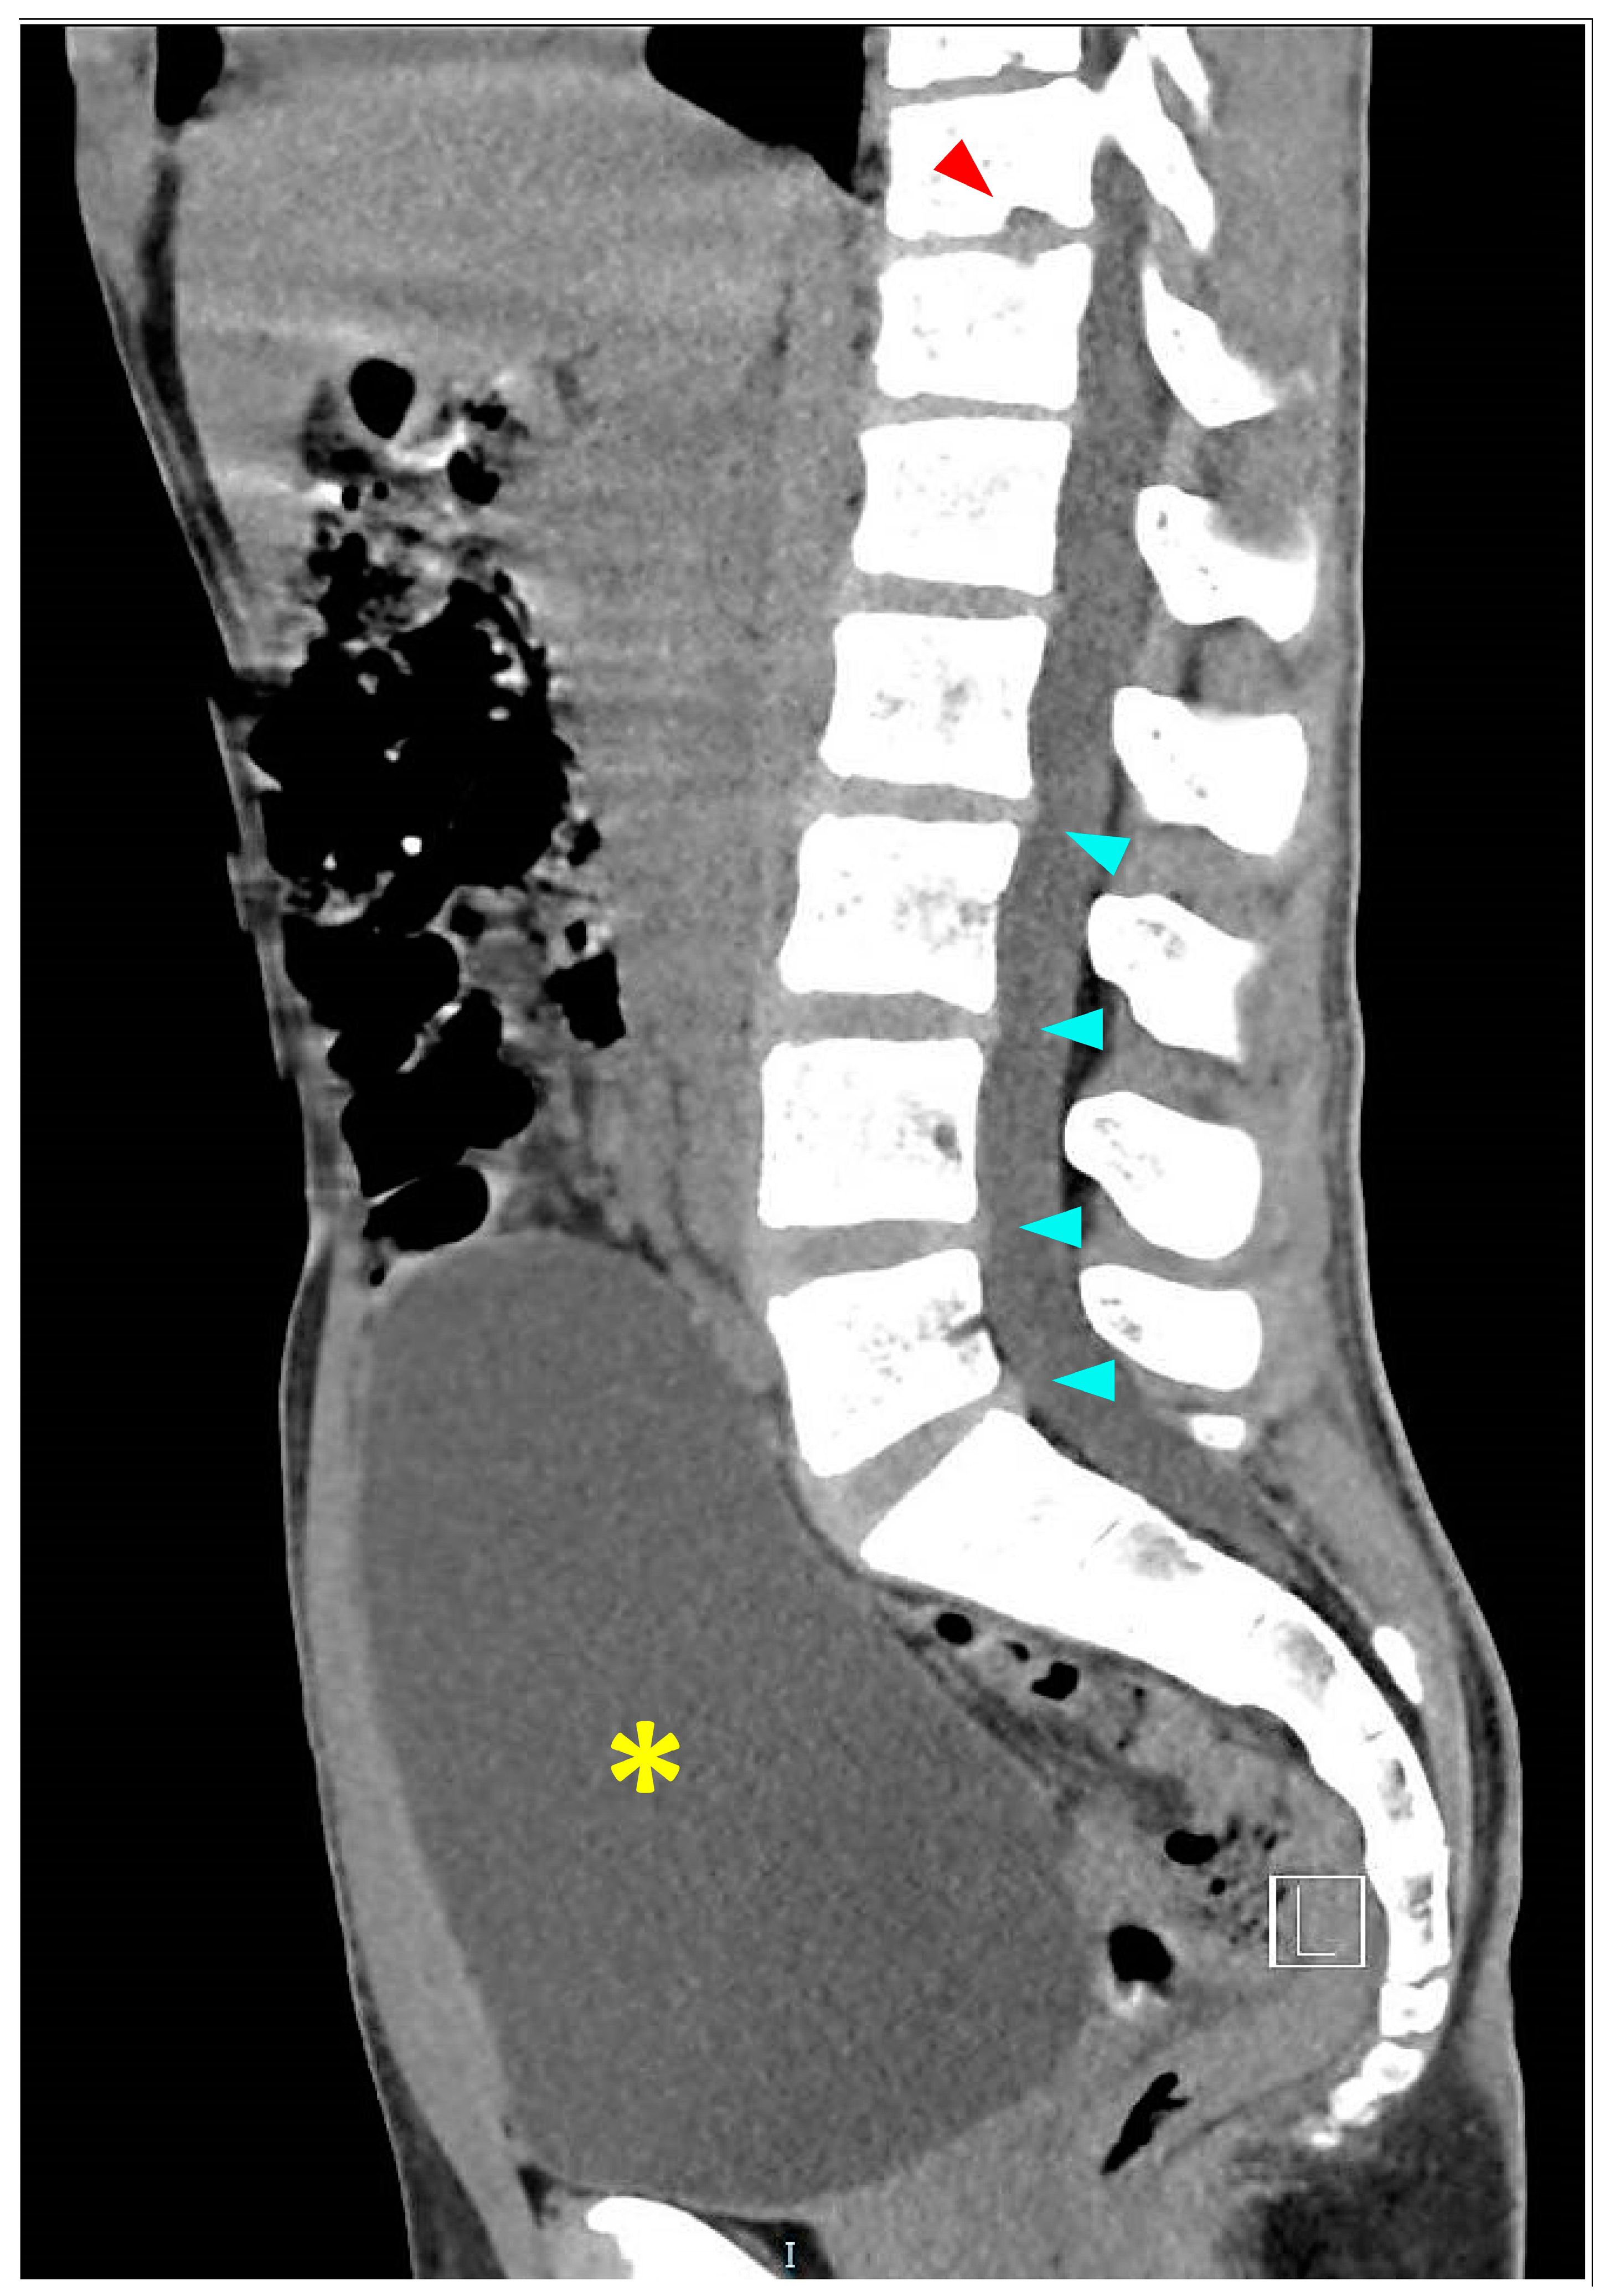

3.3.2. Imaging